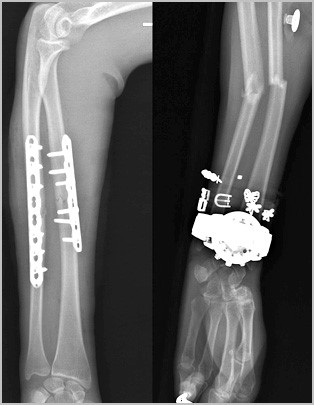

Чаще остальных фиксаторов, при переломах лучевой и локтевой кости используются пластины и специальные винты. Остеосинтез перелом лучевой и локтевой кости является «золотым стандартом» в травматологии.

Современные пластины и винты позволяют зафиксировать отломки в области перелома в правильном с анатомической точки зрения положении, а также стабильно удержать это положение до сращения перелома.

Абсолютным показанием к операции являются открытые переломы. В таких случаях на первом этапе мы стабилизируем переломы с помощью аппаратов внешней фиксации.

По заживлению ран, вторым этапом мы удаляем аппарат и производим окончательную фиксацию интрамедуллярным стержнем или пластиной. При таком подходе окончательная фиксация перелома осуществляется после заживления ран после травмы, тем самым вероятность инфекционных гнойных осложнений значительно уменьшается.